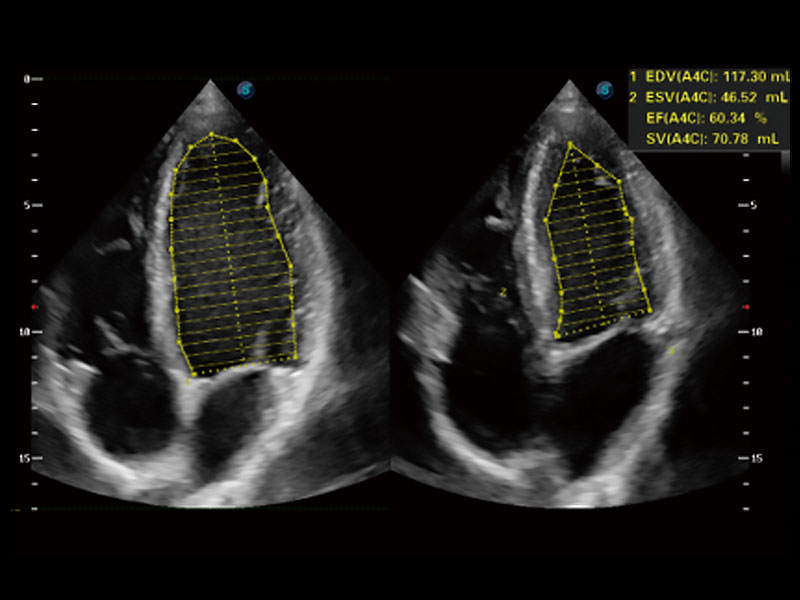

• Auto EF 心內(nèi)膜自動描跡

能夠基于左心室壁追蹤和辛普森法,自動計算射血分?jǐn)?shù),支持多個可移動點描跡,與手動測量相比,極大節(jié)省了動物醫(yī)生的時間和精力。